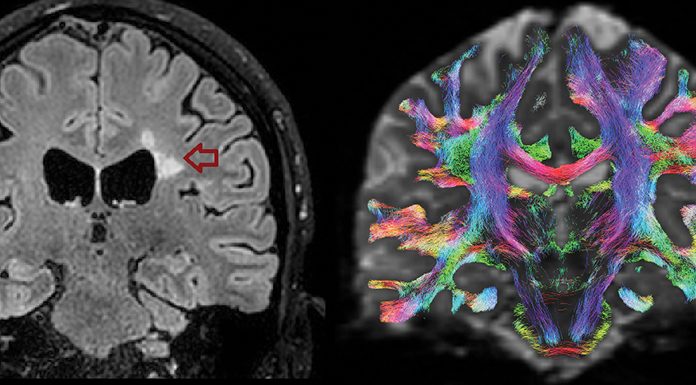

The current aim of clinicians and scientists interested in the development of MSC-based strategies for the treatment of MS is to have the ultimate demonstration that MSC can inhibit CNS inflammation and foster tissue repair as measured, clinically, by functional recovery, or visualised by magnetic resonance imaging (MRI).

With the support of the Italian MS Foundation, a phase II, proof-of-concept, international, double blind, multicentre, clinical trial (MEsenchymal StEm cells for Multiple Sclerosis – MESEMS) with autologous MSC for MS therapy is currently ongoing and aims to answer these questions. If results meet our expectations, the next stage will be to start a phase III multinational clinical trial with the support of patients’ agencies and European funding bodies.